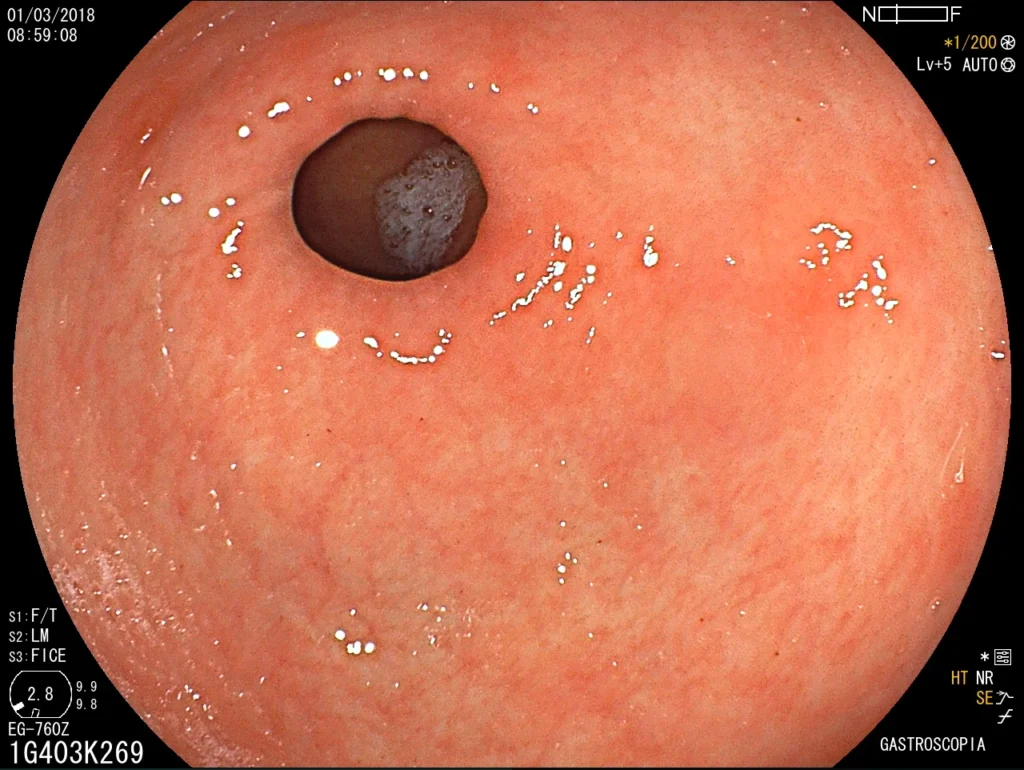

Introducción del gastroscopio bajo visión directa para examinar esófago, estómago y duodeno.